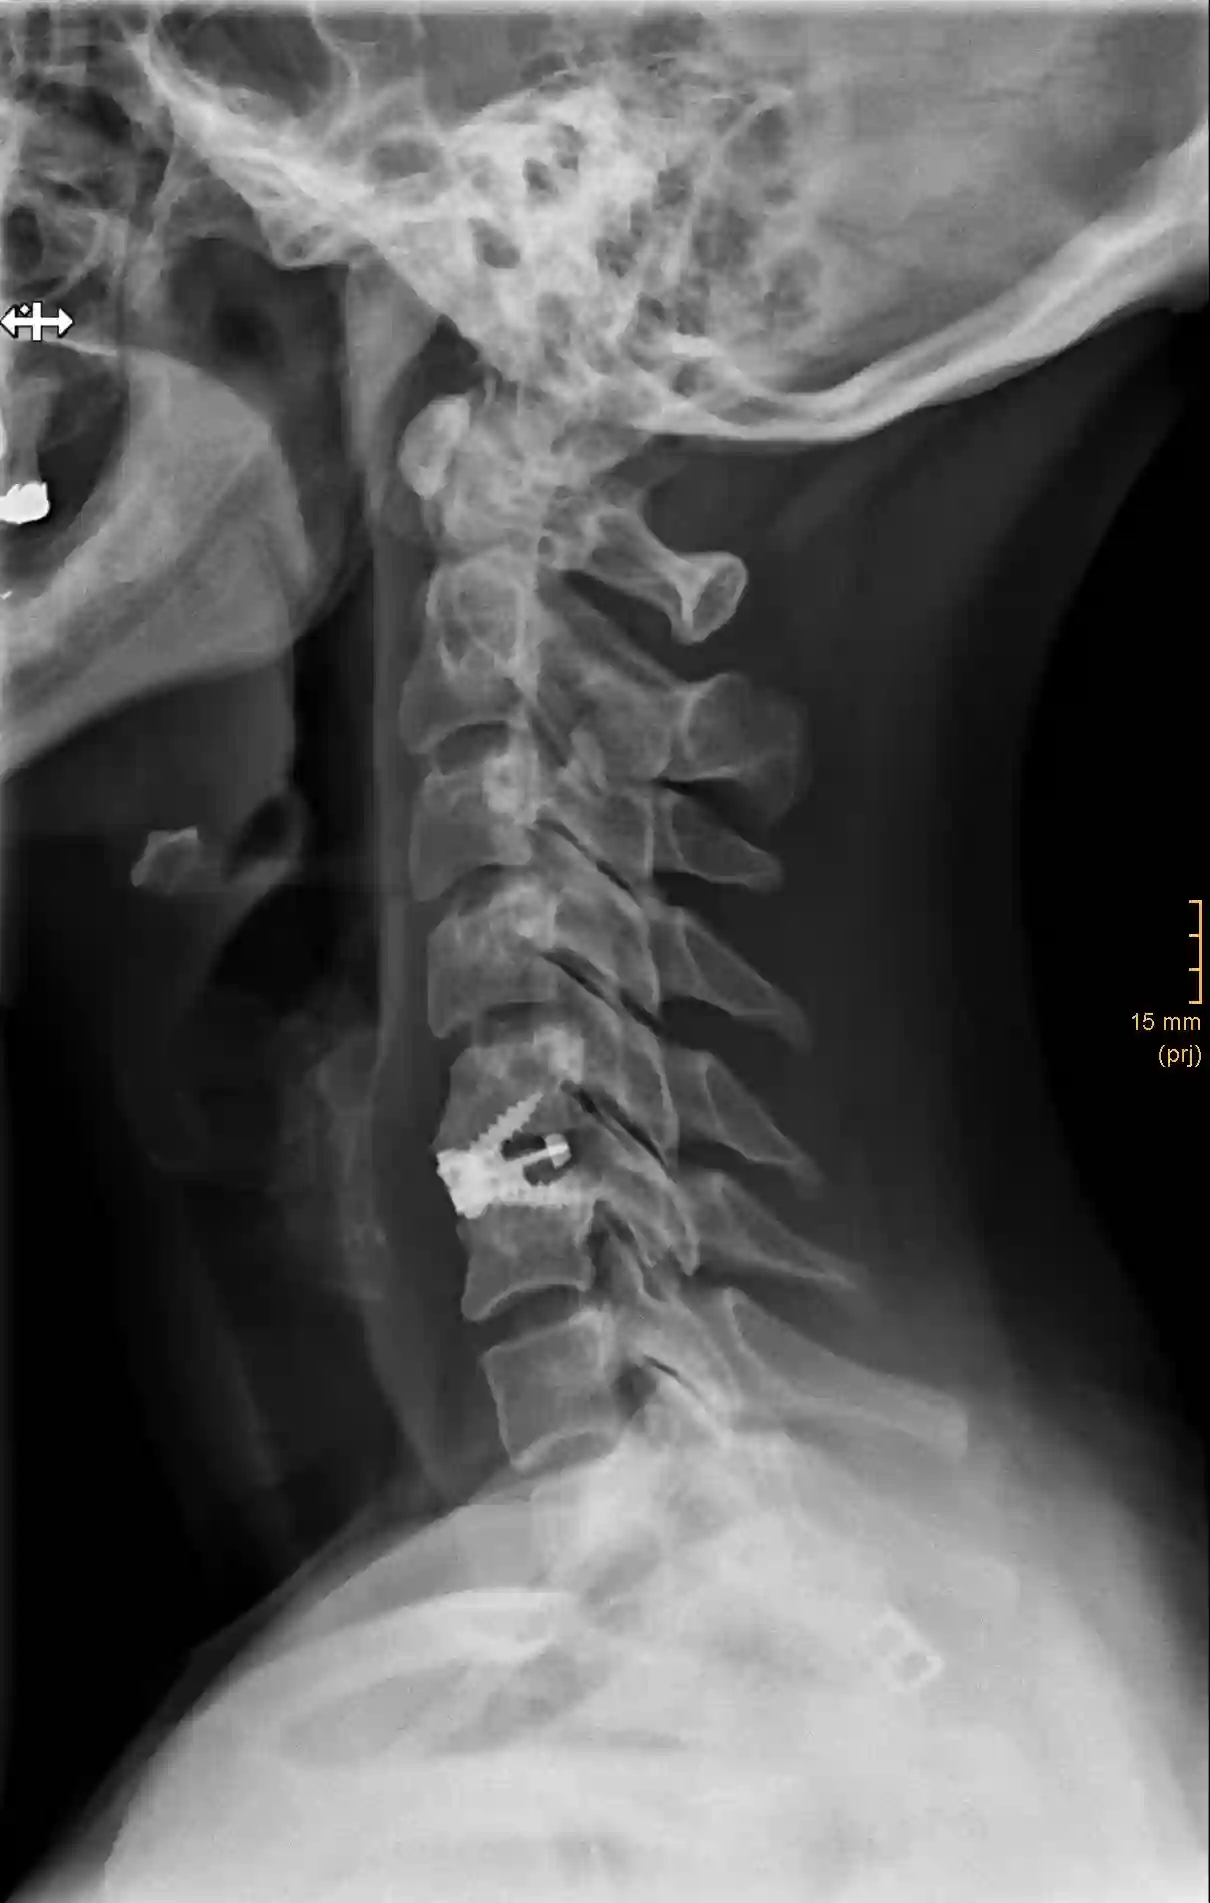

Platte

In manchen Fällen ist das zusätzliche Anbringen einer Platte sinnvoll oder auch notwendig. Beim Anbringen einer Platte sollte darauf geachtet werden, dass die Platte nicht mehr als 50 % der letzten von der Platte betroffenen Wirbelkörper abdeckt, um Anschlussosteophyten zu vermeiden[^3]

Bildgebung